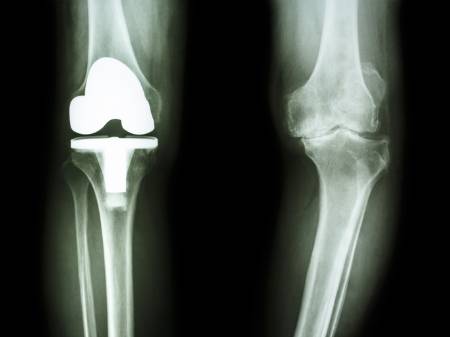

무릎 관절염의 경우 이전에는 손상되거나 기능이 저하된 부분은 인공물을 이용하거나 동종이식 등의 대체 방법으로 기능을 유지하는 치료 방법이 주류를 이뤘다. 여기에 최근에는 '재생 치료'가 정형외과를 포함한 의학 분야의 새로운 패러다임으로 자리 잡는 상황이다. 줄기세포를 이용한 치료가 대표적으로, 뼈나 지방에서 줄기세포를 포함한 세포들을 채취하여 무릎 관절에 주입하는 치료법이다. 기초 연구에서 연골세포를 분화하고 재생을 촉진한다는 결과가 밝혀졌고, 이를 바탕으로 임상까지 사용 범위가 확대되고 있다. 줄기세포를 이용한 무릎 골관절염 주사 치료에는 자가 골수와 자가 지방에서 추출하는 줄기세포가 이용되고 있다.

하지만 줄기세포 주사 치료도 결국 인공관절수술의 대안이 될 수는 없기 때문에, 전문의의 진단에 따른 정확한 치료법 선택이 중요하다. 박용범 교수는 "줄기세포 치료는 관절염 2~3단계에서 시행하는 것이 효과적"이라며 "말기인 4기인 경우에는 뼈와 뼈가 맞닿아 연골이 다 닳아 없어진 상태로 완전히 망가진 연골을 줄기세포 주사 치료를 이용한 재생은 불가능하다"고 설명했다.